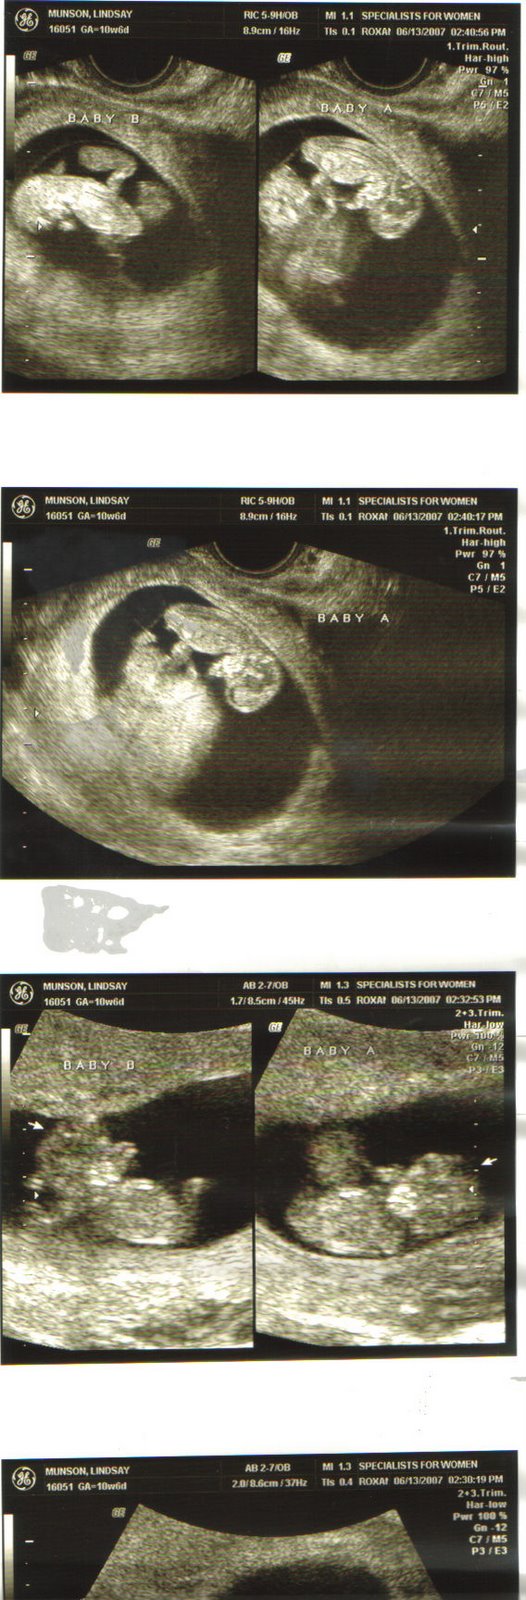

Well I had my appointment and everything is on the up and up. Baby’s heartrates were at 184 and 167. So one is more active than the other one π They are measuring perfectly and were so cute! They wiggled around a few times while we saw them and that is always fun! Oh and I lost two pounds π π I don’t think that ever happened with my pregnancy with Hayden.

We saw that they are definitely in one sac so my risk factor is pretty high. We have to see a specialist at Baylor Medical Center soon to just get a consult and make sure from his perspective that everything matches up to my OB’s. All of the risks are kind of freaking us out but we know that God is in control as always and He is the only one that can see these babies through. We appreciate all of your prayers and hope that you don’t stop! We want them to stay in there as long as they can.

Lastly……………………….we think they are boys…..the ultrasound tech said it would be very unlikely to see what they were, but when she started poking around we both saw a little “something something” on both of them….so I go back in two weeks for another ultrasound and maybe we’ll know for sure then. That was like the one scenario that we didn’t have a second potential name for…..so we’ll be putting our thinking caps on now π And Mel, yes…I do go more often and get ultrasounds every time since I am high risk.